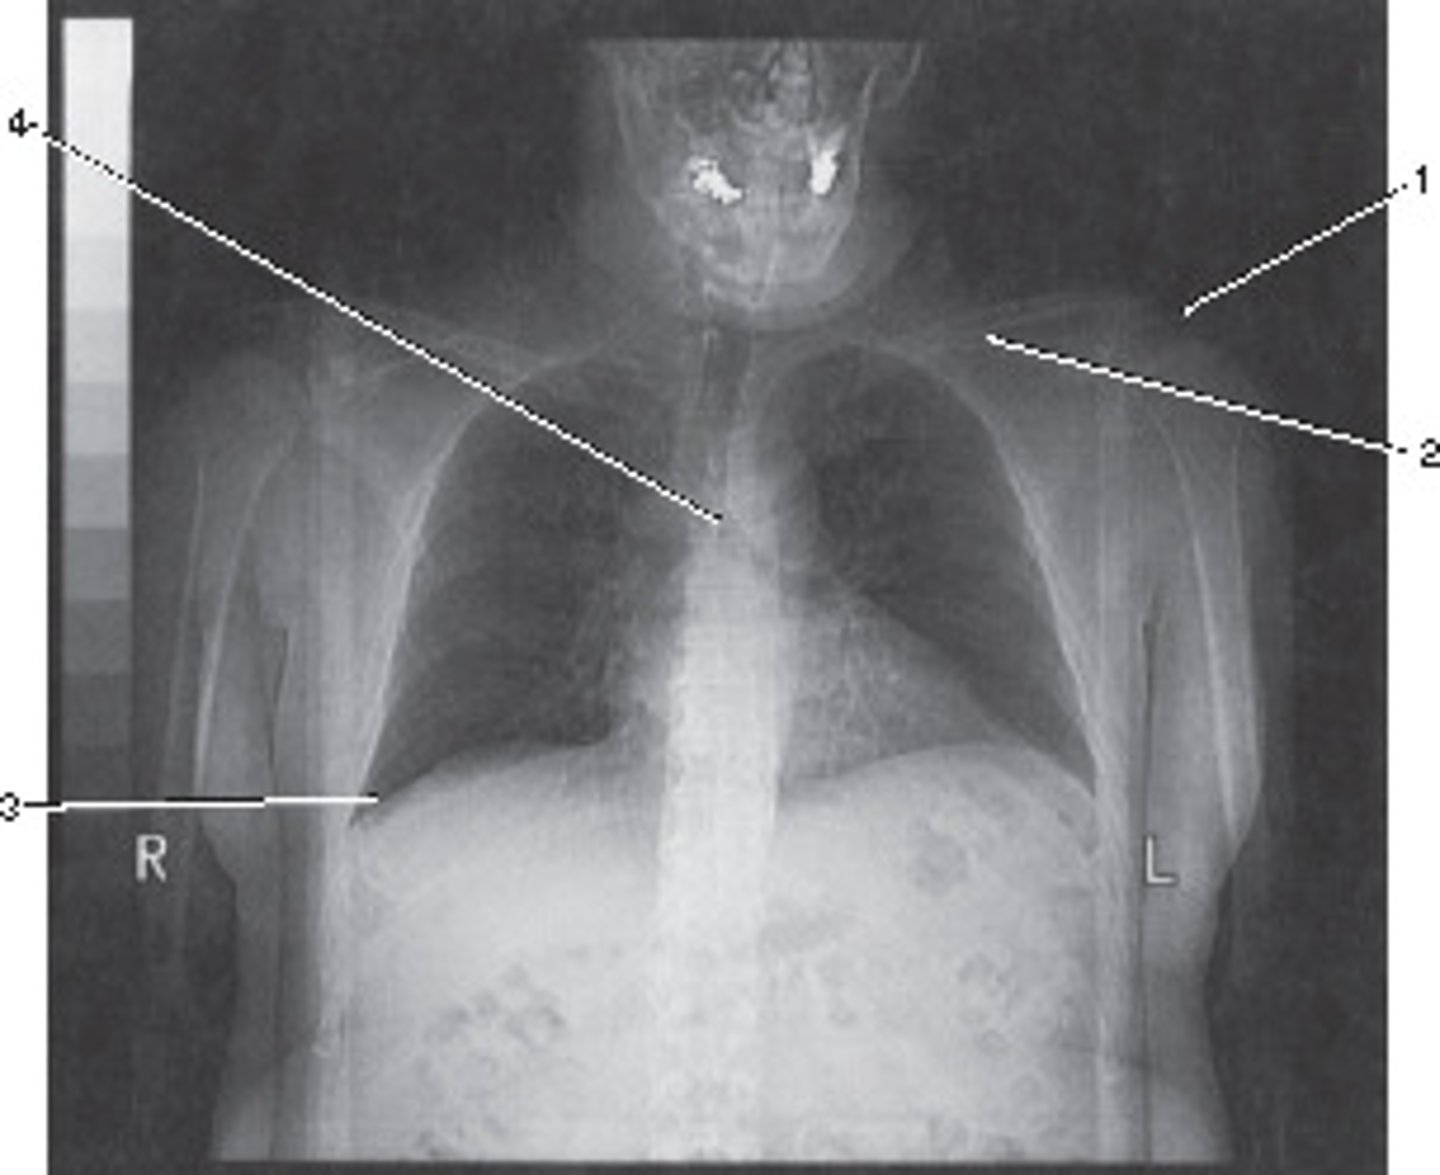

0 degrees;

The Azimuth setting refers to the relationship betyween the x-ray tube and detectors during scout of localizer production.

What azimuth setting was used to obtain this image?

<p>What azimuth setting was used to obtain this image?</p>

Abdomen and Adomen/Pelvis

This localizer (scanogram) could be used to program which of the following examinations?

<p>This localizer (scanogram) could be used to program which of the following examinations?</p>